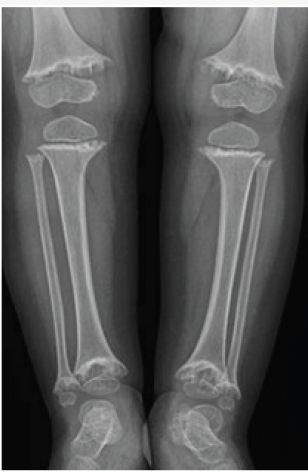

Figure 5: Healing rickets bowing of the tibiae.

Complete healing and restoration of normal structures occurs in nutritional rickets. However distortion/sclerosis of spongiosa in affected segment may occur after healing & may remain visible for several years. Cortical thickening of segments of bone involved during active stage also may persist. Angular deformities secondary to pathological fractures result in deformities like knock-knee, bow leg and sabre shin (Figure 5).